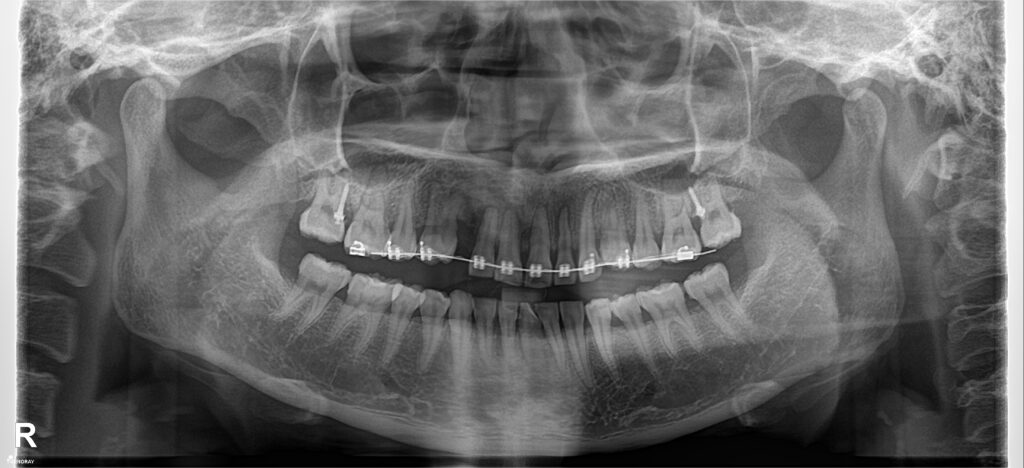

Phim chụp so sánh kết quả trước điều trị và kết quả sau điều trị.